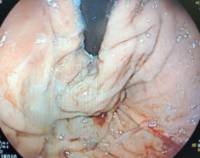

Imagen 2 –Post-procedimiento- : Misma visión del cardias en retroflexión, ya realizada la funduplicatura anterior, con mínimo sangrado, visualizando un agarre perfecto sobre el tubo del endoscopio)